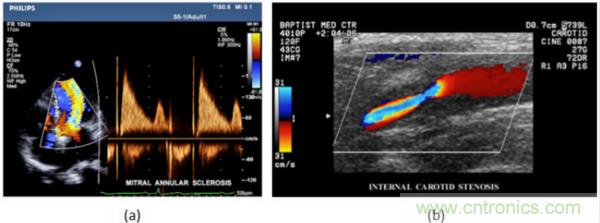

在CW和PW多普勒模式中,流信息是從一個(gè)聚焦聲束中獲得的,類(lèi)似于A(yíng)模式成像。在20世紀(jì)80年代,研究人員基于彩色多普勒技術(shù)完成了血流分布的二維信息可視化。彩色多普勒處理也是基于B模式/PW模式信號(hào)路徑。從感興趣區(qū)域收集多幀RF數(shù)據(jù)。由于感興趣區(qū)域中的血液流動(dòng)導(dǎo)致圖像幀之間存在數(shù)據(jù)差異。相域中的自相關(guān)和時(shí)域中的互相關(guān)兩種算法可從RF數(shù)據(jù)中提取數(shù)據(jù)方差(即血流速度和方向信息):。根據(jù)預(yù)定義的顏色漸變條相應(yīng)地映射包括速度和方向的血流信息。通常,藍(lán)色和紅色代碼分別識(shí)別朝向和遠(yuǎn)離換能器移動(dòng)的血流。當(dāng)流速增加時(shí)使用更亮的顏色,反之亦然。顏色映射的2D分布始終疊加在B模式圖像上,以實(shí)時(shí)同時(shí)顯示個(gè)體解剖結(jié)構(gòu)和血流。它對(duì)于診斷心血管疾病,如血管閉塞和心臟瓣膜反流,極其有用。典型的彩色多普勒?qǐng)D像如下圖所示,(b)顯示頸動(dòng)脈狹窄引起的血流流速變化。

圖7.彩色多普勒成像:(a)以彩色多普勒和CW模式獲得的圖像(由Philips提供); (b)顯示頸動(dòng)脈狹窄的彩色多普勒(由GE提供)